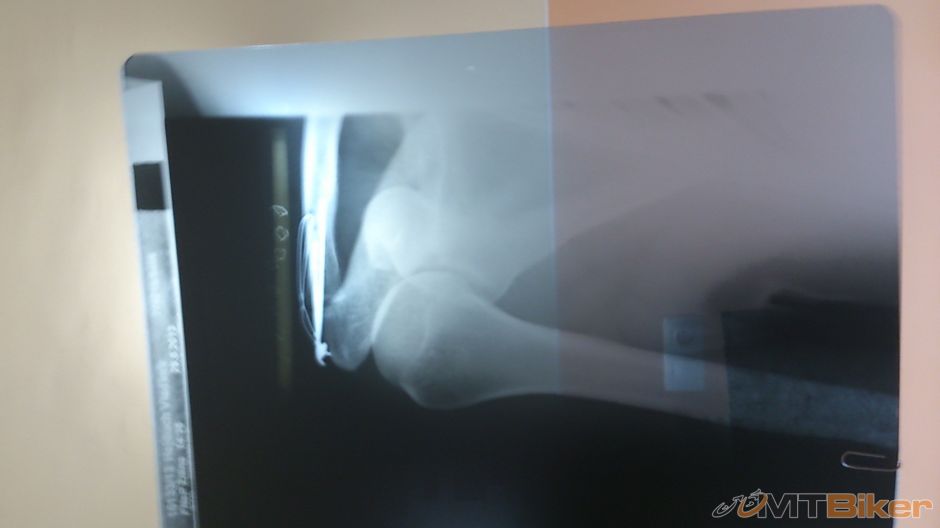

Az teraz som objavil toto vlakno, tak prispejem mojou troskou...vyhrabal som RTG. Pad v mensej rychlosti (cca 20km/h), najprv odrazenie od kamena v kaluzi, pad do druhej blatistej kaluze na lavy bok. Pravdepdobne tam bolo kopec kamenov a ja som drzal rajdy... Najprv mi nic nebolo, chcel som pokracovat vo svojom prvom MTB maratone aj dalej, ale akosik som nemohol stlacit lavu brzdu, inak som nebol ani osuchany, ani doranany, vsetko OK. Zbehol+zjazdil som spat do startu kde som uz chytil triasku. Vysledok - dve zlomene zaprstne kosticky lavej ruky, kde je jedna bohuzial posunuta a nutna operacia, ktora prebehla v celkovej anestezii. Prespikovali mi tu kost klincom, ktory mi dalej trcal az von z ruky. Inak pocas celej doby ma nic nebolelo, bolest som zazil az pri rehabilitacii, kedze som mal tie prsty dlho fixovane a vsetko svalstvo (+slachy) ochablo a musel som to cez bolest posutpne rozpohybovat. Este pikoska k vybratiu tej chirurgickej ocele...bola vytahovana ambulantne kliestami na klince co mate aj doma (bez anestezie), to preto mi ho nechali trcat von pri operacii. Klinec mi ostal ako suvenir.